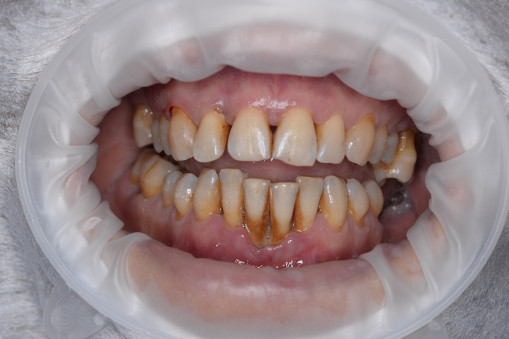

А прежде, чем вы посмотрите фотографии «до» и «после» лечения слизистой оболочки полости рта, проведенных в нашей клинике, хочу поблагодарить большое количество наших пациентов, которые поверили, прониклись нашей концепцией, и мы вместе, именно вместе победили болезни десны, гингивит и пародонтит!

До/после лечения